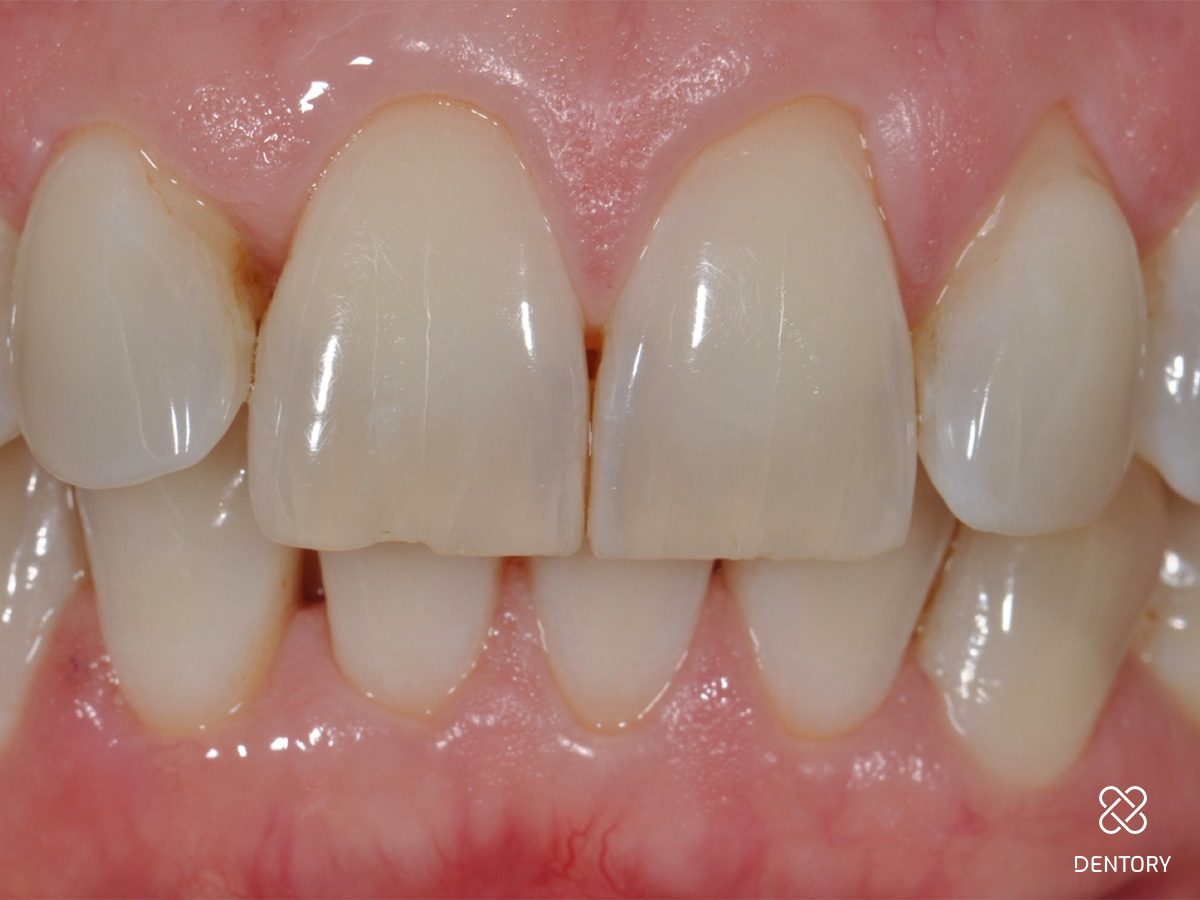

Abbildung 1

Ausgangssituation: Frontalansicht.